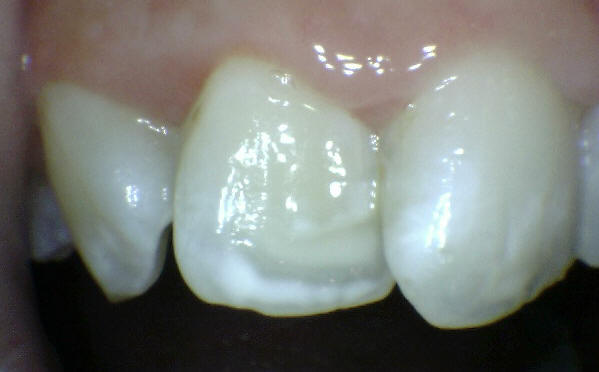

El examen visual debe emprenderse con los dientes completamente secos y con una buena iluminación.  El uso de amplificación de imagen también puede ayudar en el diagnóstico. El uso de una sonda se restringe al levantamiento de placa y detritos de comida.

El diente al lavarse y secarse con la jeringa triple deja expuesto esmalte blanquecino escarchado o opaco que delata un proceso de desmineralización, debido a que el agua se evapora de los microporos. Ver círculos rojos

Codificación  ICDAS y manejo individual de las lesiones

Código 1

Código 2

Código 3

Código 4

Código 5

Caries Inicial

Caries Moderada

Caries Severa

MNO

MNO /MOPD

MOPD:

Una mancha oscura de dentina que se observa a través del esmalte intacto,  adyacente a la fosa y reborde marginal,  indica la presencia de desmineralización. (Imagen 0229)